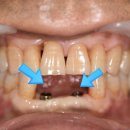

대구 시지바름플란트치과의원입니다. 치아가 흔들려요 시지치과 최근 위와 같은 주소로... 환자분께 가장 잘 맞았던 임시치아와 같은 형태로 기공소에 보철 기공을 의뢰하고 나서, 보철을 올려주기만 하면...

대구 시지바름플란트치과의원(20240920)

치과 내 기공소가 있는 부천역치과를 찾고 계신다면 의료진 모두가 바른 치아 건강을 위해 힘쓰는 바른약속치과를 찾아주세요^^ 감사합니다! 사진을 누르시면 예약 페이지로 이동합니다

바른약속치과 부천본원(20230309)

자연치아를 살리고 싶어서 찾고 찾아보다가 멀리서 잠실 더바름치과 까지 왔습니다. 꼭 살리고... 좋은 보철물을 위해서는 치과의사의 노하우도 중요하지만 *. 본을 잘 뜨고 *. 기공소에서 좋은 보철물을...

Dentistry, Combination ART & SCIENCE(20241216)